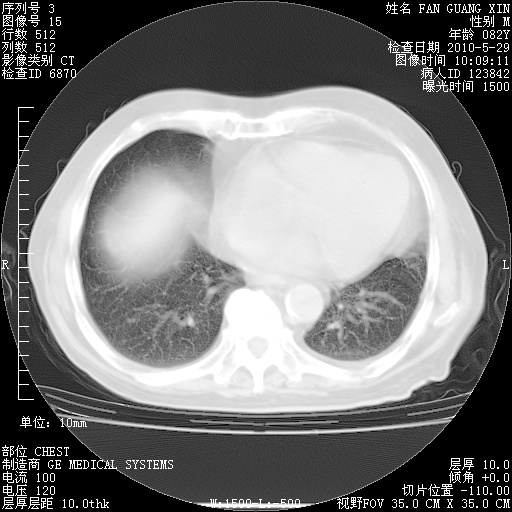

再治疗10天后的肺部CT

再治疗10天后的肺部CT 纵膈窗

阅读此次胸部CT,肺间质渗出性改变较入院时有吸收。目前从体温、白细胞、中性分叶明显增高,肯定存在细菌感染(发生医院感染哦,若无消化道及泌尿系统等感染的依据,肺部感染可能大)。若你院头孢哌酮舒巴坦钠耐药率较高,同意你的方案,若48小时体温仍高,可考虑使用碳青霉稀类抗菌药物,同时可予超声雾化、注意滴数时加大液体量。白蛋白33.30g/L较低哦,需加强营养等支持治疗。